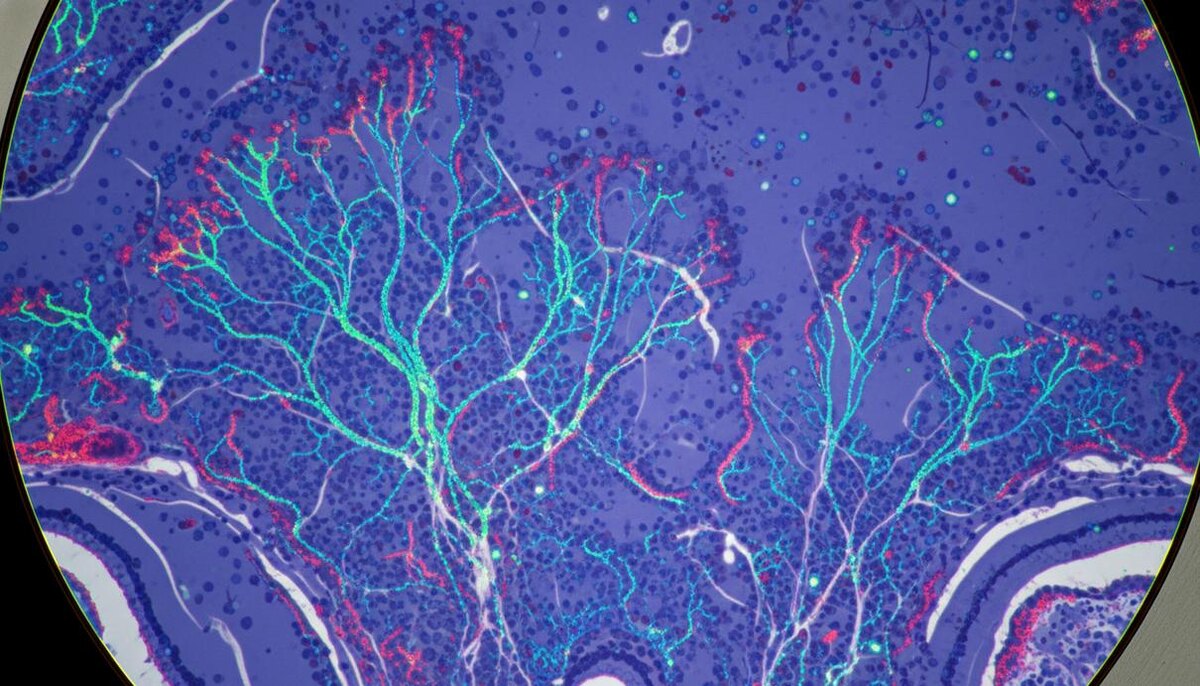

Лабораторные эксперименты показали, что избыток FTL1 меняет структуру нервных клеток. Вместо разветвленных сетей, характерных для здорового мозга, нейроны формировали упрощенные одиночные отростки. Кроме того, белок негативно влиял на клеточный метаболизм. Однако применение соединений, стимулирующих энергетический обмен, позволило нейтрализовать этот эффект.